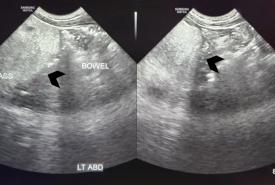

Paediatric Mesenteric Lipoblastoma: A Remarkable Rarity